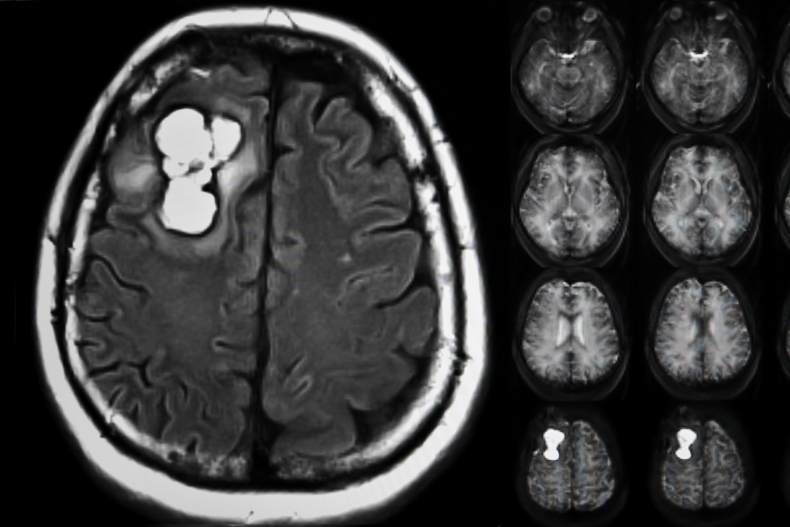

Her beyin tümörü aynı değildir. Belirtilerden tedaviye, patoloji raporundan prognoza kadar hastalar ve yakınları için sade bir anlatımla açıklıyoruz.

Beyin tümörünün bulunduğu bölgeye göre kalıcı ve geçici beyin hasarı kalabilir. Bazı durumlarda tümör beyne zarar verebilir.

Beyin biyopsisi şüpheli neoplastik lezyonların tanısında, etyolojisi bilinmeyen nörolojik hastalıklarda tanı ve tedavi amacıyla uygulanmaktadır.

Baş ağrısı, mide bulantısı, kusma, el veya kolda güç kaybı, sara nöbeti beyin tümörü belirtilerindendir.

Beyin tümörü ameliyatı süreci, riskleri, kullanılan teknolojiler ve iyileşme süreci hakkında detaylı bilgiler